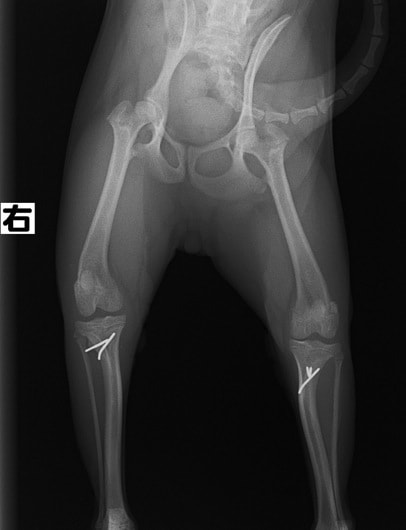

■ 症例24 キャバリア 7か月

左右膝蓋骨内方脱臼(左:グレードⅣ 右:グレードⅢ)

以前から左右後肢の跛行が認められ、整形外科学的検査・レントゲン検査により左右の膝蓋骨脱臼が認められた。症状が重度である左膝の膝蓋骨脱臼整復術を行った。外科手技は縫工筋及び内側広筋の解放、脛骨粗面の外側転位、滑車ブロック形造溝術、内外側関節方の縫縮を実施した。術後一か月時点で、左の膝蓋骨は安定しており経過は良好である。

本症例は成長期における重度の膝蓋骨脱臼であり、術後の再発の可能性もあるため、経過をしっかりと観察していく必要がある。また、今回手術を実施していない右膝に関しても経過を観察し、手術を検討していくこととする。